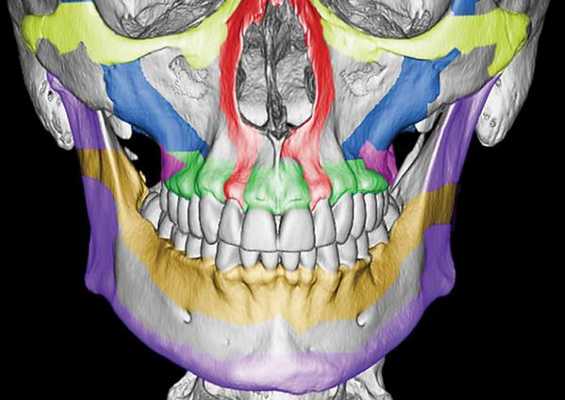

Чтобы понимать, как ломается верхняя челюсть следует сначала остановиться на её анатомии. Верхняя челюсть (лат. maxilla) — парная кость, которая у взрослого человека представляет собой единую систему. Она имеет две больших полости (верхнечелюстные пазухи) и участвует в формировании ещё трёх полостей — глазницы и полости носа. По своему строению это ажурная, тонкая структура, находящаяся в передне-средней части черепа.

Она соединена с другими костями лицевого скелета и основания черепа: скуловой, лобной, носовой, слёзной, решётчатой, клиновидной, нёбной.

Выделяют так называемые отростки верхней челюсти: скуловой отросток (соединяется со скуловой костью и формирует ширину лица ), лобный отросток (формирует плавность профиля спинки носа и опосредованно участвует в формировании очертаний глазниц), нёбный отросток (формирует твёрдое небо, срастается по средней линии нёбного шва с противоположной верхнечелюстной костью) и альвеолярный отросток (содержит в себе зубы).

Верхняя челюсть представляет собой достаточно прочную структуру, благодаря местам особой прочности — контрфорсам, которые представляют собой костные утолщения. Различают лобно-носовой, альвеолярно-скуловой, крыловидно-нёбный и нёбный контрфорсы. Забегая вперёд, стоит сказать, что при оперативном лечении переломов верхней челюсти эти "линии" используются для надёжной, ригидной фиксации (остеосинтеза) повреждённых костей.

Однако в строении верхней челюсти есть и участки сниженной прочности. Они находятся вдоль швов, соединяющих верхнюю челюсть с другими костями лицевого скелета, а также с костями основания черепа.Таким образом, можно понять, что при чрезмерном механическом воздействии верхняя челюсть чаще всего ломается именно в местах перехода от прочных участков к слабым или просто в слабых местах [4] .

По этой причине линия перелома часто проходит не строго по анатомическим границам верхней челюсти, а смещается на соседние, связанные с ней кости. Это объясняет, почему в практике челюстно-лицевых хирургов встречаются не столько переломы самой верхней челюсти, сколько её "выламывание" с фрагментами других костей лица и основания черепа.

Чаще всего переломы классифицируют по Рене Ле Фору. Этот французский хирург систематизировал и описал формирующиеся повреждения костей средней зоны лица экспериментально: на головы свежих человеческих трупов он оказывал разные по направлению и силе воздействия по типу тупой травмы. Именно так и было обнаружено, что большинство линий переломов проходит по трём типам [1] :

- | тип — нижний, или горизонтальный тип, перелом Герена — Ле Фора. Перелом проходит над альвеолярным отростком и нёбным отростком через боковую и переднюю поверхности верхней челюсти, от крыловидных отростков основной кости к краю грушевидного отверстия.

- || тип — средний, или пирамидальный перелом, суборбитальный перелом. Линия перелома проходит через корень носа, внутреннюю стенку глазницы и далее — через нижнеглазничную щель кпереди по нижней стенке глазницы к месту альвеолярно-скулового контрфорса с переломом крыловидных отростков. Проще говоря, верхняя челюсть единым блоком "отсоединяется" от остальных костей средней зоны лица.

- ||| тип — верхний тип (поперечный, суббазальный, он же черепно-лицевое разъединение). Самый грозный вид перелома верхней челюсти, когда происходит отрыв верхней челюсти вместе со скуловыми костями от мозгового черепа. Как правило сочетается с тяжёлыми повреждениями головного мозга [3] .